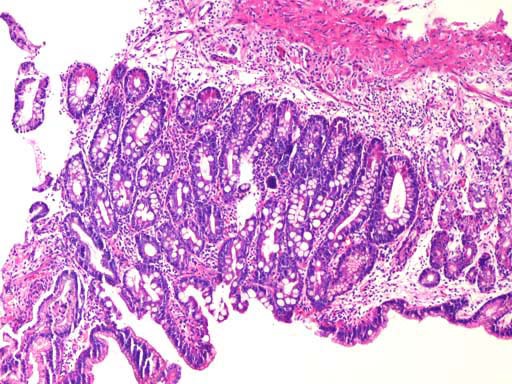

170.胃窦部黏膜组织活检,镜下如图所示,胃黏膜发生的有关病变的描述,错误的是